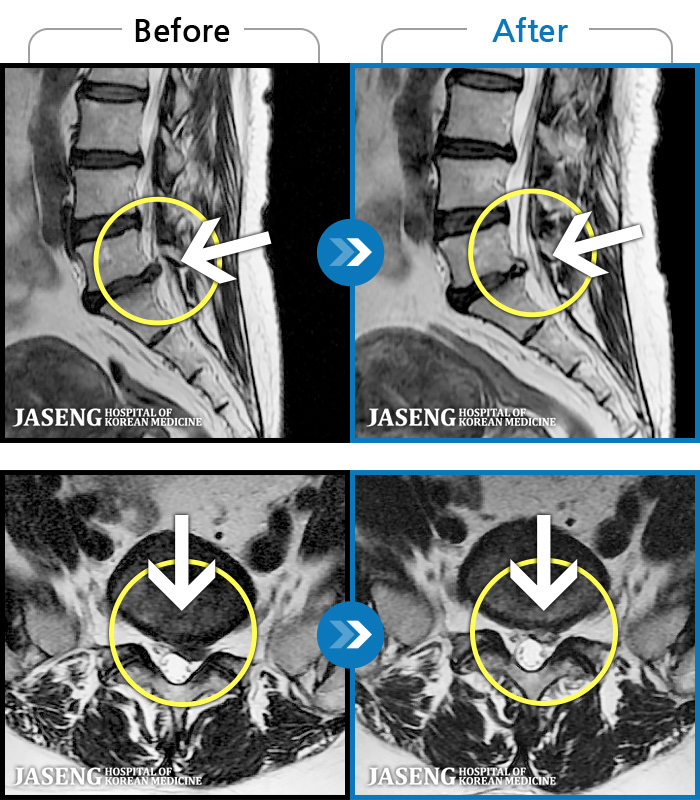

- MRI ġ

MRI ġ

63 MRI ũ ʸ Ȯϼ.